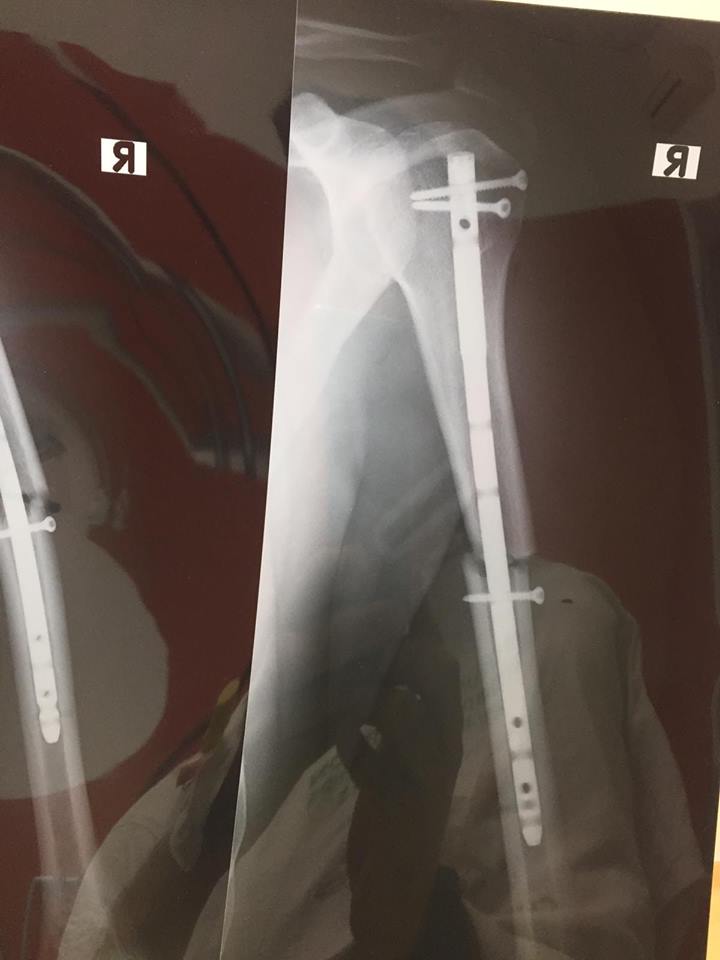

Celebrul sportiv sătmărean Mani Gyenes a suferit un accident cu urmări grave și se află internat într-o clinică de specialitate. Și asta după ce a fost victima unui incident, în urma căruia a suferit o fractură la braţul drept. Rider-ul sătmărean speră să se recupereze cât mai repede pentru o nouă ediție a raliului Dakar. Totul s-a întâmplat în urma unei banale sesiuni foto. Mani a sărit cu motocicleta peste o movilă, dar a aterizat prost, căzând pe mână. ”Anul acesta, ultimele saptamani dinaintea plecarii catre Raliul Dakar vor decurge intr-un mod diferit. In weekend, in timpul unei sesiunii foto, am suferit o fractura de humerus si acum ma concentrez pe recuperare. Voi face tot ce imi sta in putinta sa ajung la finisul din Lima”, a spus Mani Gyenes. Reamintim că sătmăreanul Mani Gyenes a încheiat, în 21 ianuarie 2018, din nou cea de a 40-a editie a Raliului Dakar, cea mai dificilă dintre cele organizate în America de Sud. Rider-ul sătmărean a reușit să termine pentru a șaptea oară raliul. Mai mult, a izbutit ca la finalul celor 14 etape să se claseze pe 23 la general și 13 la clasa SuperProducție.